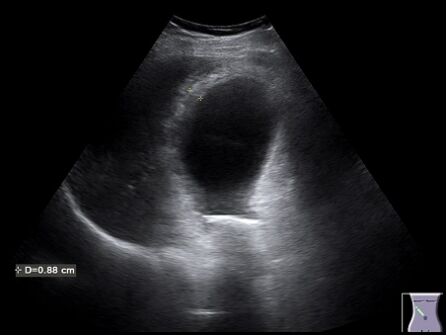

63.右上腹部超音波掃描時,發現一囊狀構造橫徑超過4公分,壁厚超過3公釐,內有高回音結構且具有 後側音影(acoustic shadowing),以及陽性超音波墨菲氏徵象(positive sonographic Murphy's sign),下圖最有可能的診斷為何? (A)急性結石性膽囊炎(acute calculous cholecystitis) (B)急性無結石性膽囊炎(acute acalculous cholecystitis) (C)急性氣腫性膽囊炎(acute emphysematous cholecystitis) (D)膽結石性腸阻塞(gallstone ileus)